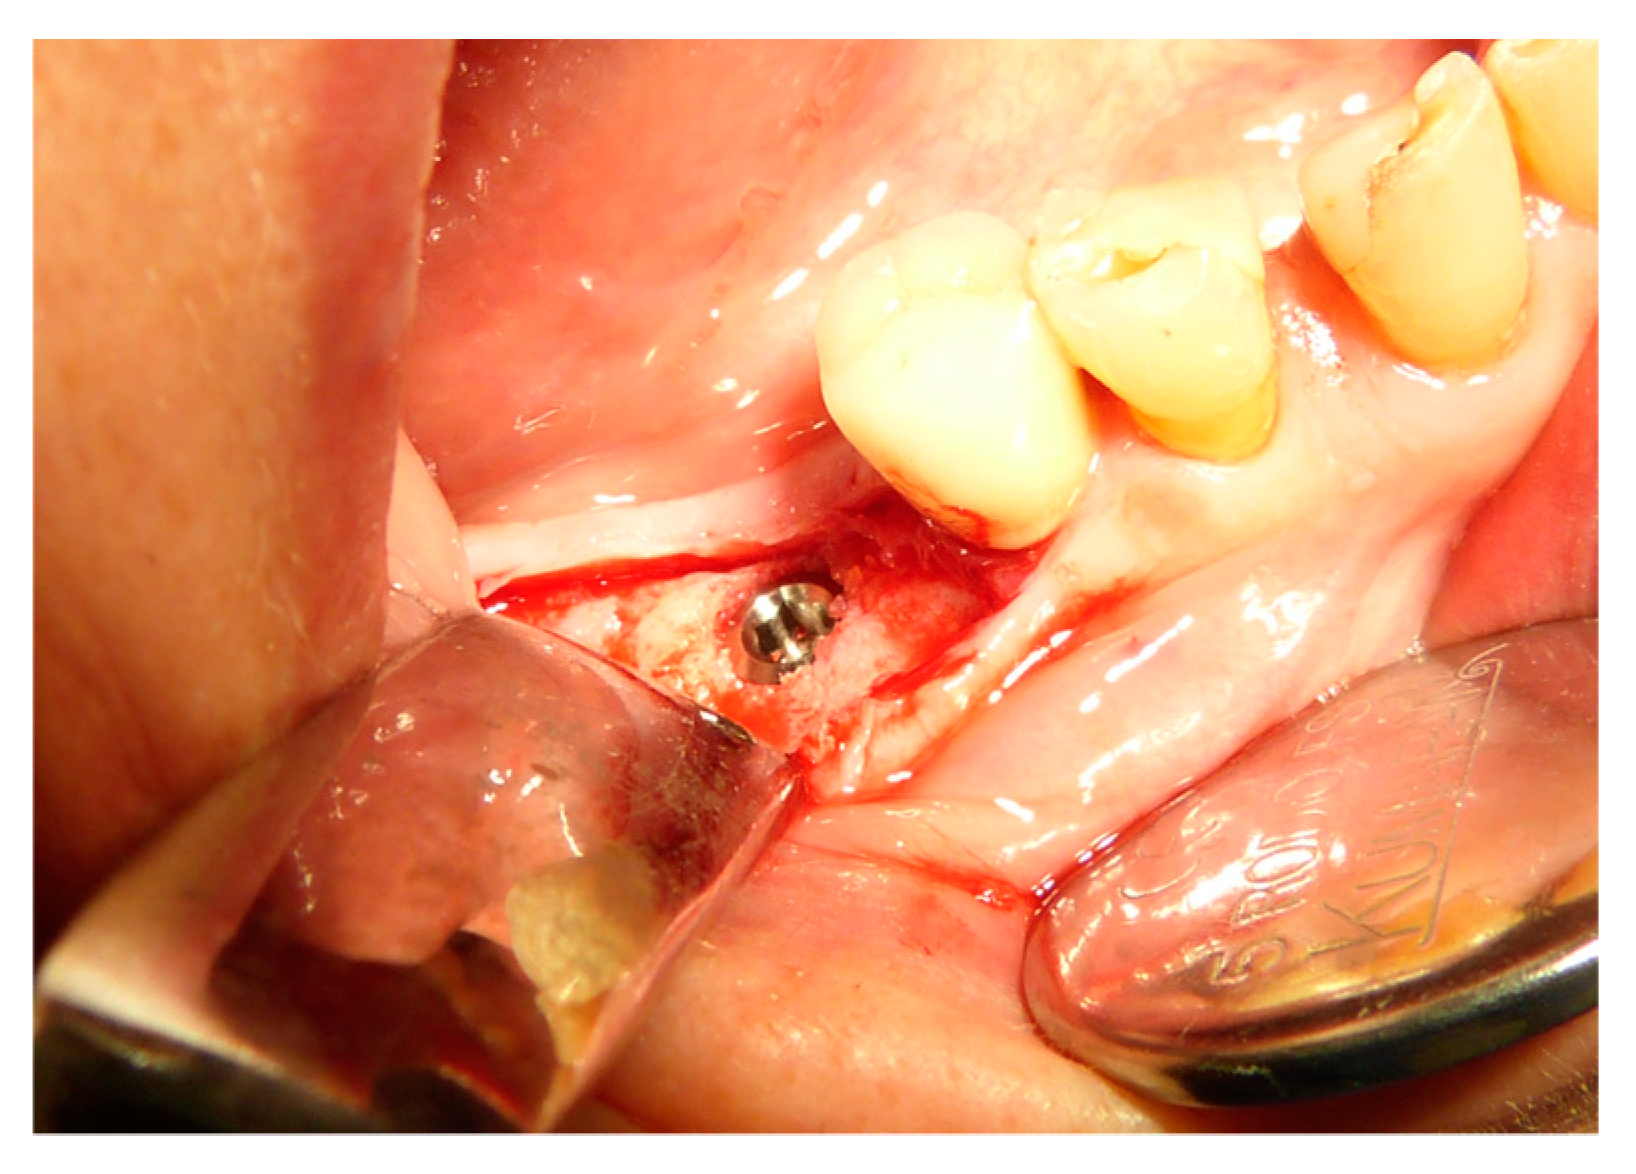

The vertical average defect was 9.16 mm, buccal lateral/palatal 7.0 mm, and mesio-distal 10.3 mm. The measurements were intraoperatively performed with a millimeter periodontal probe. The endodontic material mechanically cleaned before the tooth was placed inside the Tooth Transformer device. The endodontic material was removed using a drill bur with the attention to cut the canal in excess with the aim to remove all the cement. No surgical complications were registered. Pre and post-operative X-rays (section from CBCT) were collected from the same case (Figure 1, Figure 2, Figure 3 and Figure 4). After four months, 13 histological and histomorphometrical evaluations were performed (Figure 5). The Bone Volume/Total Volume average (BV%) was 41.47 (S.D. ± 11.51), the Residual Graft/Total Volume average (Graft%) was 16.60 (S.D. ± 7.09), and the Vital Bone/Total Bone average (VB%) was 21.89 (S.D. ± 9.72). No extraneous material (gutta-percha or cement) was detected in all samples (Table 3).

Figure 10. Implant placement in the regenerated bone after three months.